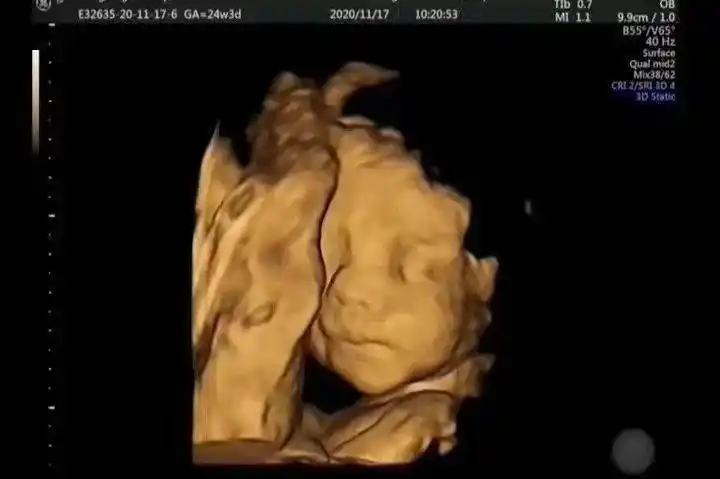

科普胎儿的第一张照片四维超声

图片尺寸720x479